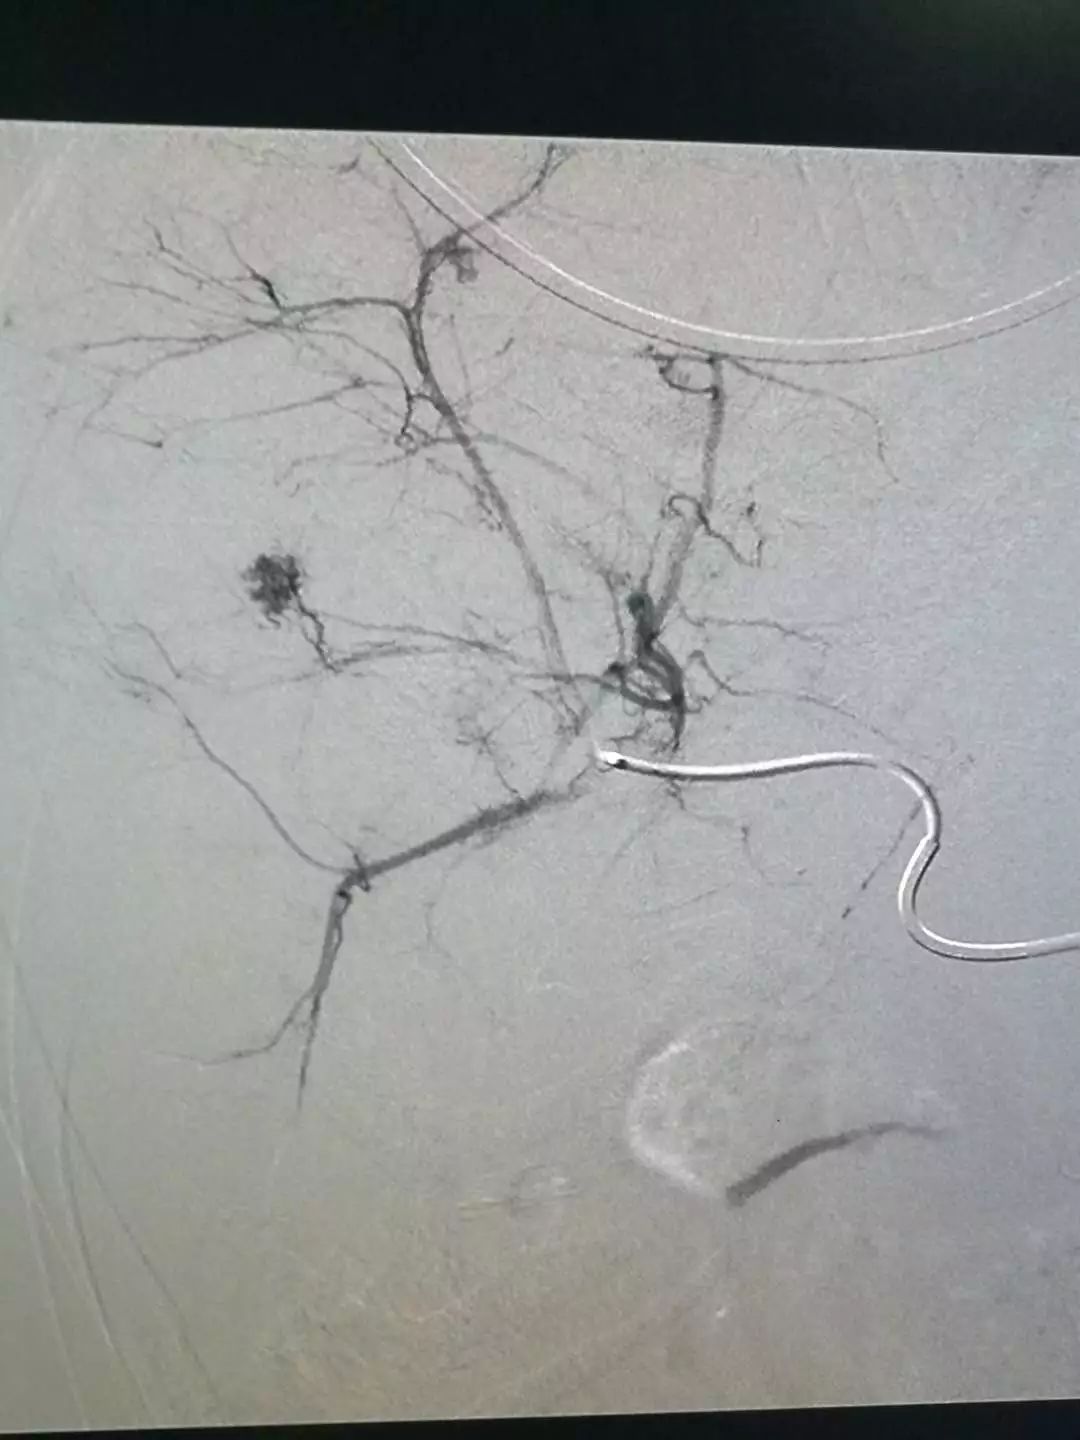

肝血管瘤造影染色

双侧子宫动脉造影,肌瘤以右侧子宫动脉供血为主